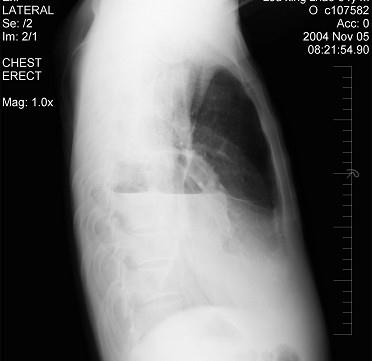

问题 男性患者,64岁,咳嗽高热多日,无痰中带血,X线检查如图,最合理的诊断是 ( )

选项 A.右侧胸腔积液 B.右侧胸腔积液并肺脓肿 C.右肺炎 D.右肺不张 E.右支气管扩张

答案 B